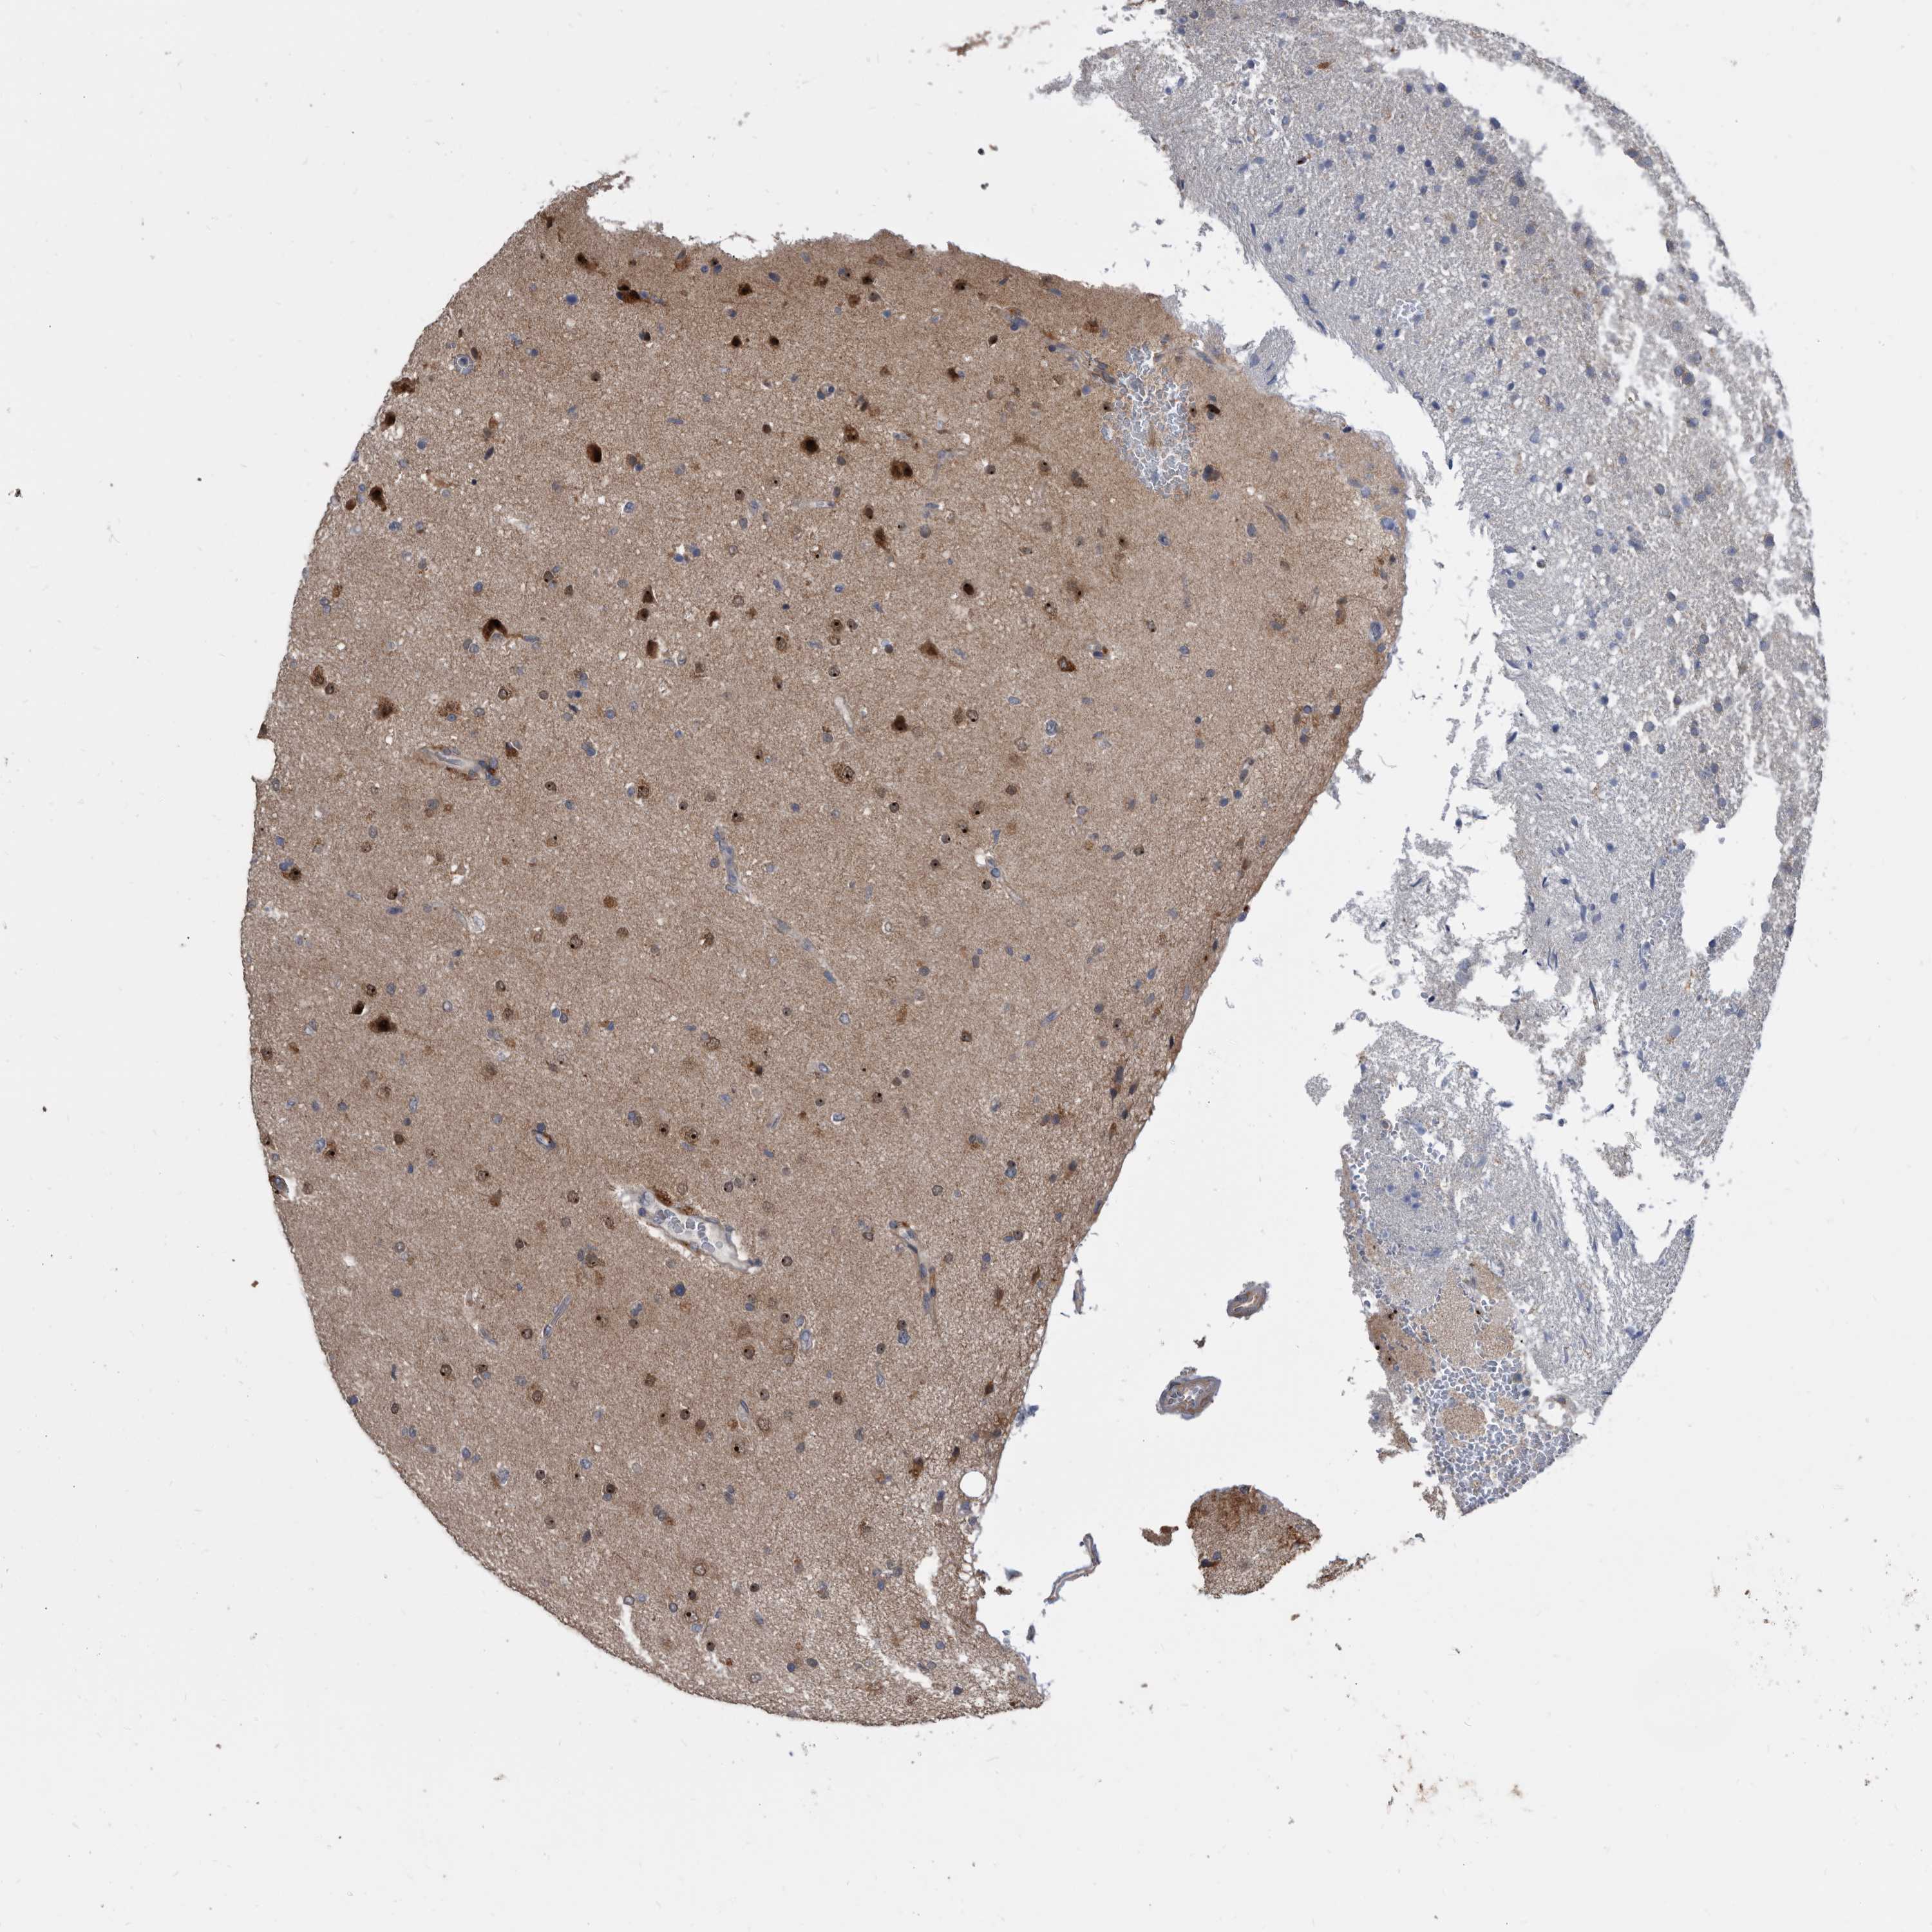

GLIOMA - Protein expressioni

A mouse-over function shows sample information and annotation data. Click on an image to view it in a full screen mode. Samples can be filtered based on level of antibody staining by selecting one or several of the following categories: high, medium, low and not detected. The assay and annotation is described here.

Note that samples used for immunohistochemistry by the Human Protein Atlas do not correspond to samples in the TCGA dataset.

Antibody stainingi

Antibody staining in the annotated cell types in the current human tissue is reported as not detected, low, medium, or high, based on conventional immunohistochemistry profiling in selected tissues. This score is based on the combination of the staining intensity and fraction of stained cells.

Each image is clickable and will lead to virtual microscopy that enables deeper exploration of all samples and also displays staining intensity scores, fraction scores and subcellular localization as well as patient and tissue information for each sample.

Antibody HPA029700

Antibody HPA029701

Antibody HPA029702

Antibody HPA029703

Staining

High

Medium

Low

Not detected

Intensity

Strong

Moderate

Weak

Negative

Quantity

>75%

75%-25%

<25%

None

Location

Nuclear

Cytoplasmic/membranous

Cytoplasmic/membranous,nuclear

Glioma, malignant, High grade

Glioma, malignant, Low grade

Glioblastoma, NOS